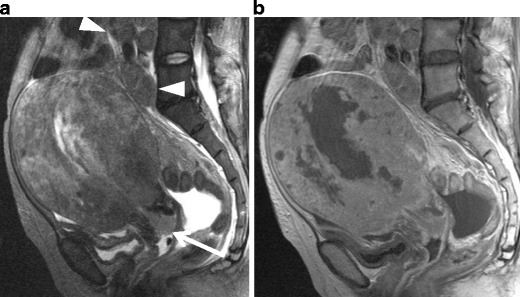

Leiomyosarcoma in a 60-year-old woman. a Sagittal T2-weighted image demonstrates an irregular-shaped large mass of heterogeneous intensity in the posterior wall of the uterus (arrows). b Postcontrast T1-weighted images with fat suppression demonstrate multifocal, unenhanced areas of necrosis within the tumor